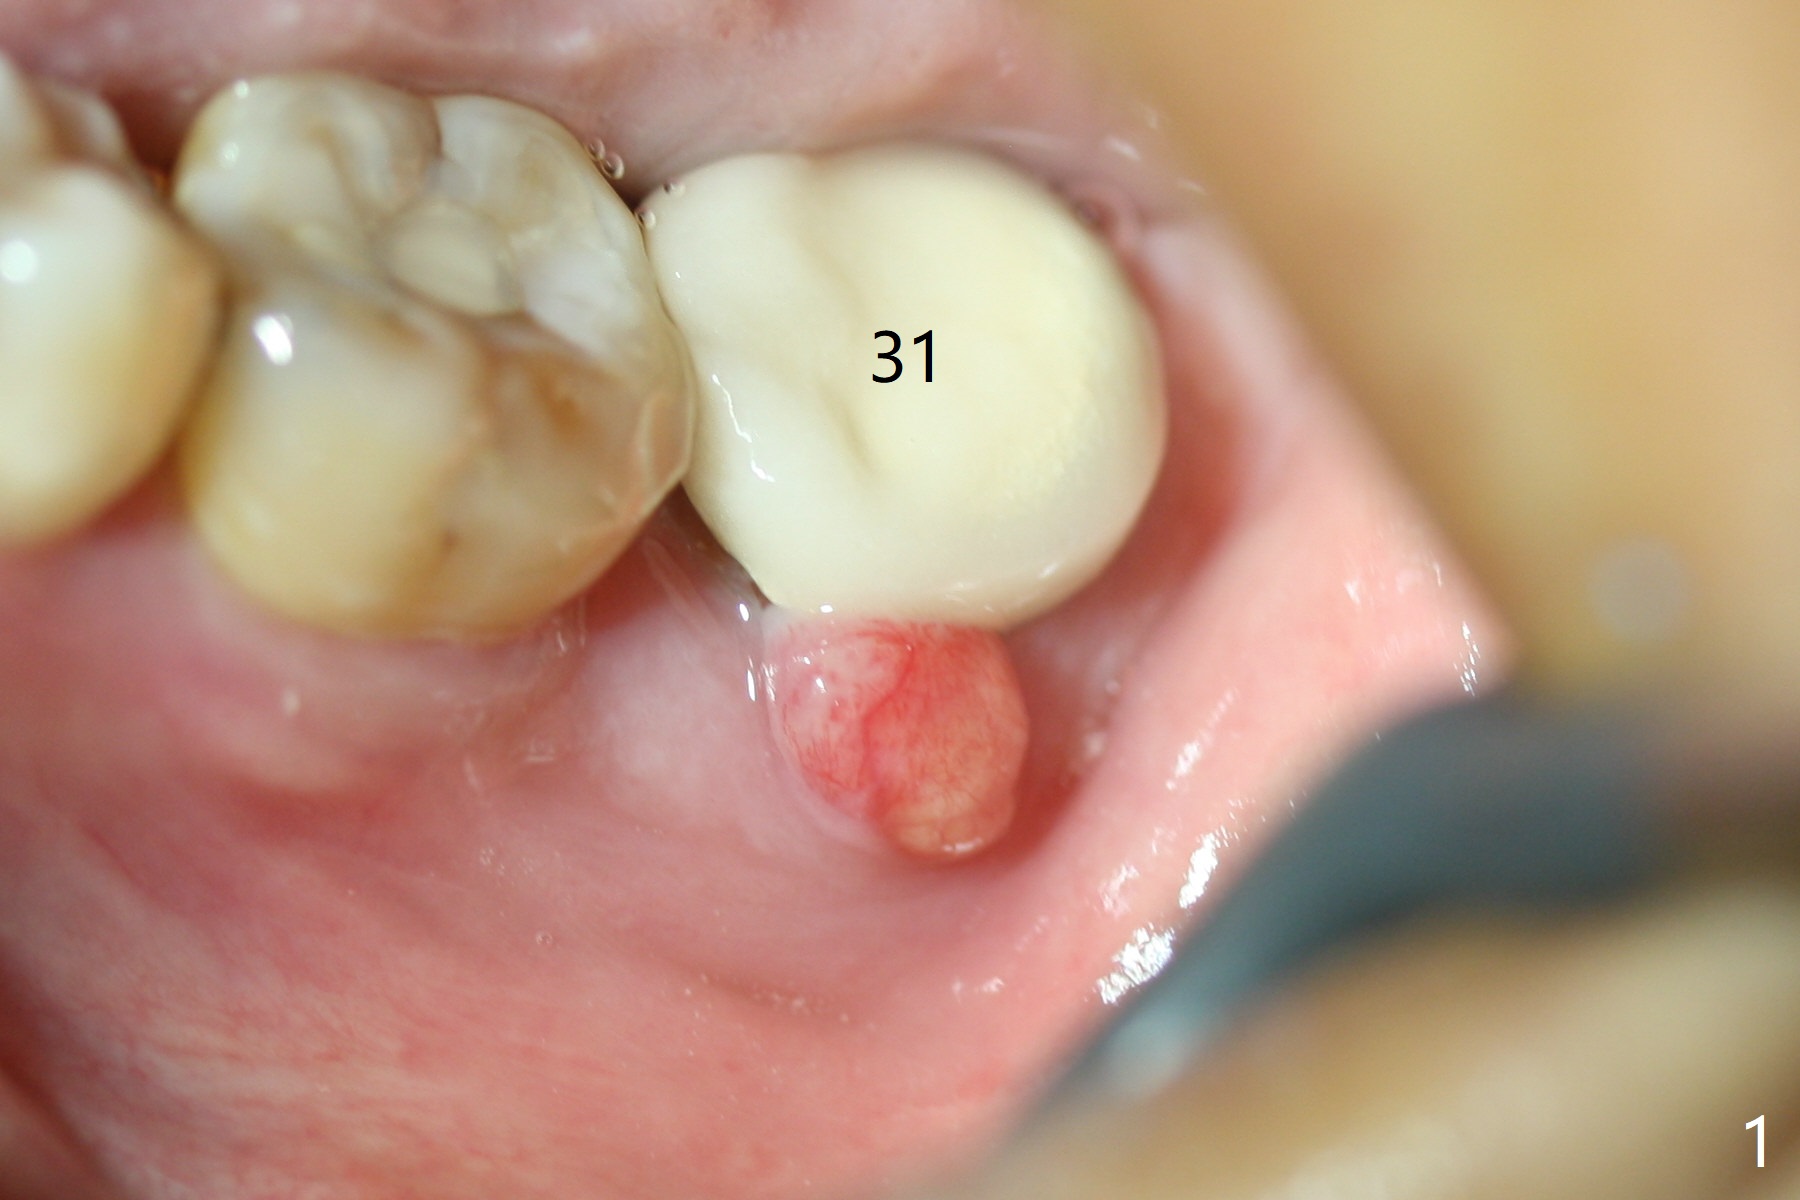

The patient with chronic buccal abscess at #31 is nervous.  After extraction, a 7x11 mm tapered implant drops into the single socket, which is close to the Inferior Alveolar Canal (Fig.2).  The bottom of the socket is sensitive to manipulation (explorer) after infiltration anesthesia.  A 8x14 mm tapered tap is placed without binding, neither is a 8x14 mm cylindrical implant.  The implant stability does not increase when Vera (.2-1.0 mm) or Vanilla (.5-1.0 mm) Graft is placed.  Socket preservation is finished with Collagen plug and 6-month membrane (Fig.3,4).